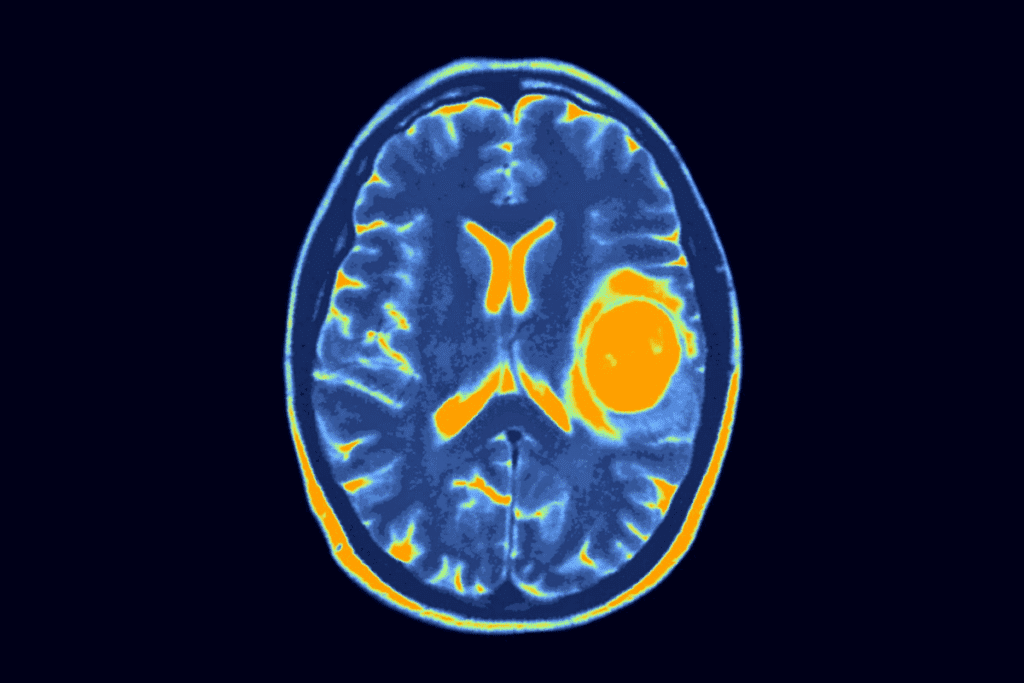

Imaging Technologies and Protocols

Advanced imaging is vital for catching brain tumors early. MRI (Magnetic Resonance Imaging) is often used. It’s very sensitive and shows the brain’s details well.

For those at high risk, the protocols might include:

- Annual or biennial MRI scans

- Contrast-enhanced MRI for better visualization

- Specific sequences like FLAIR or T1-weighted images